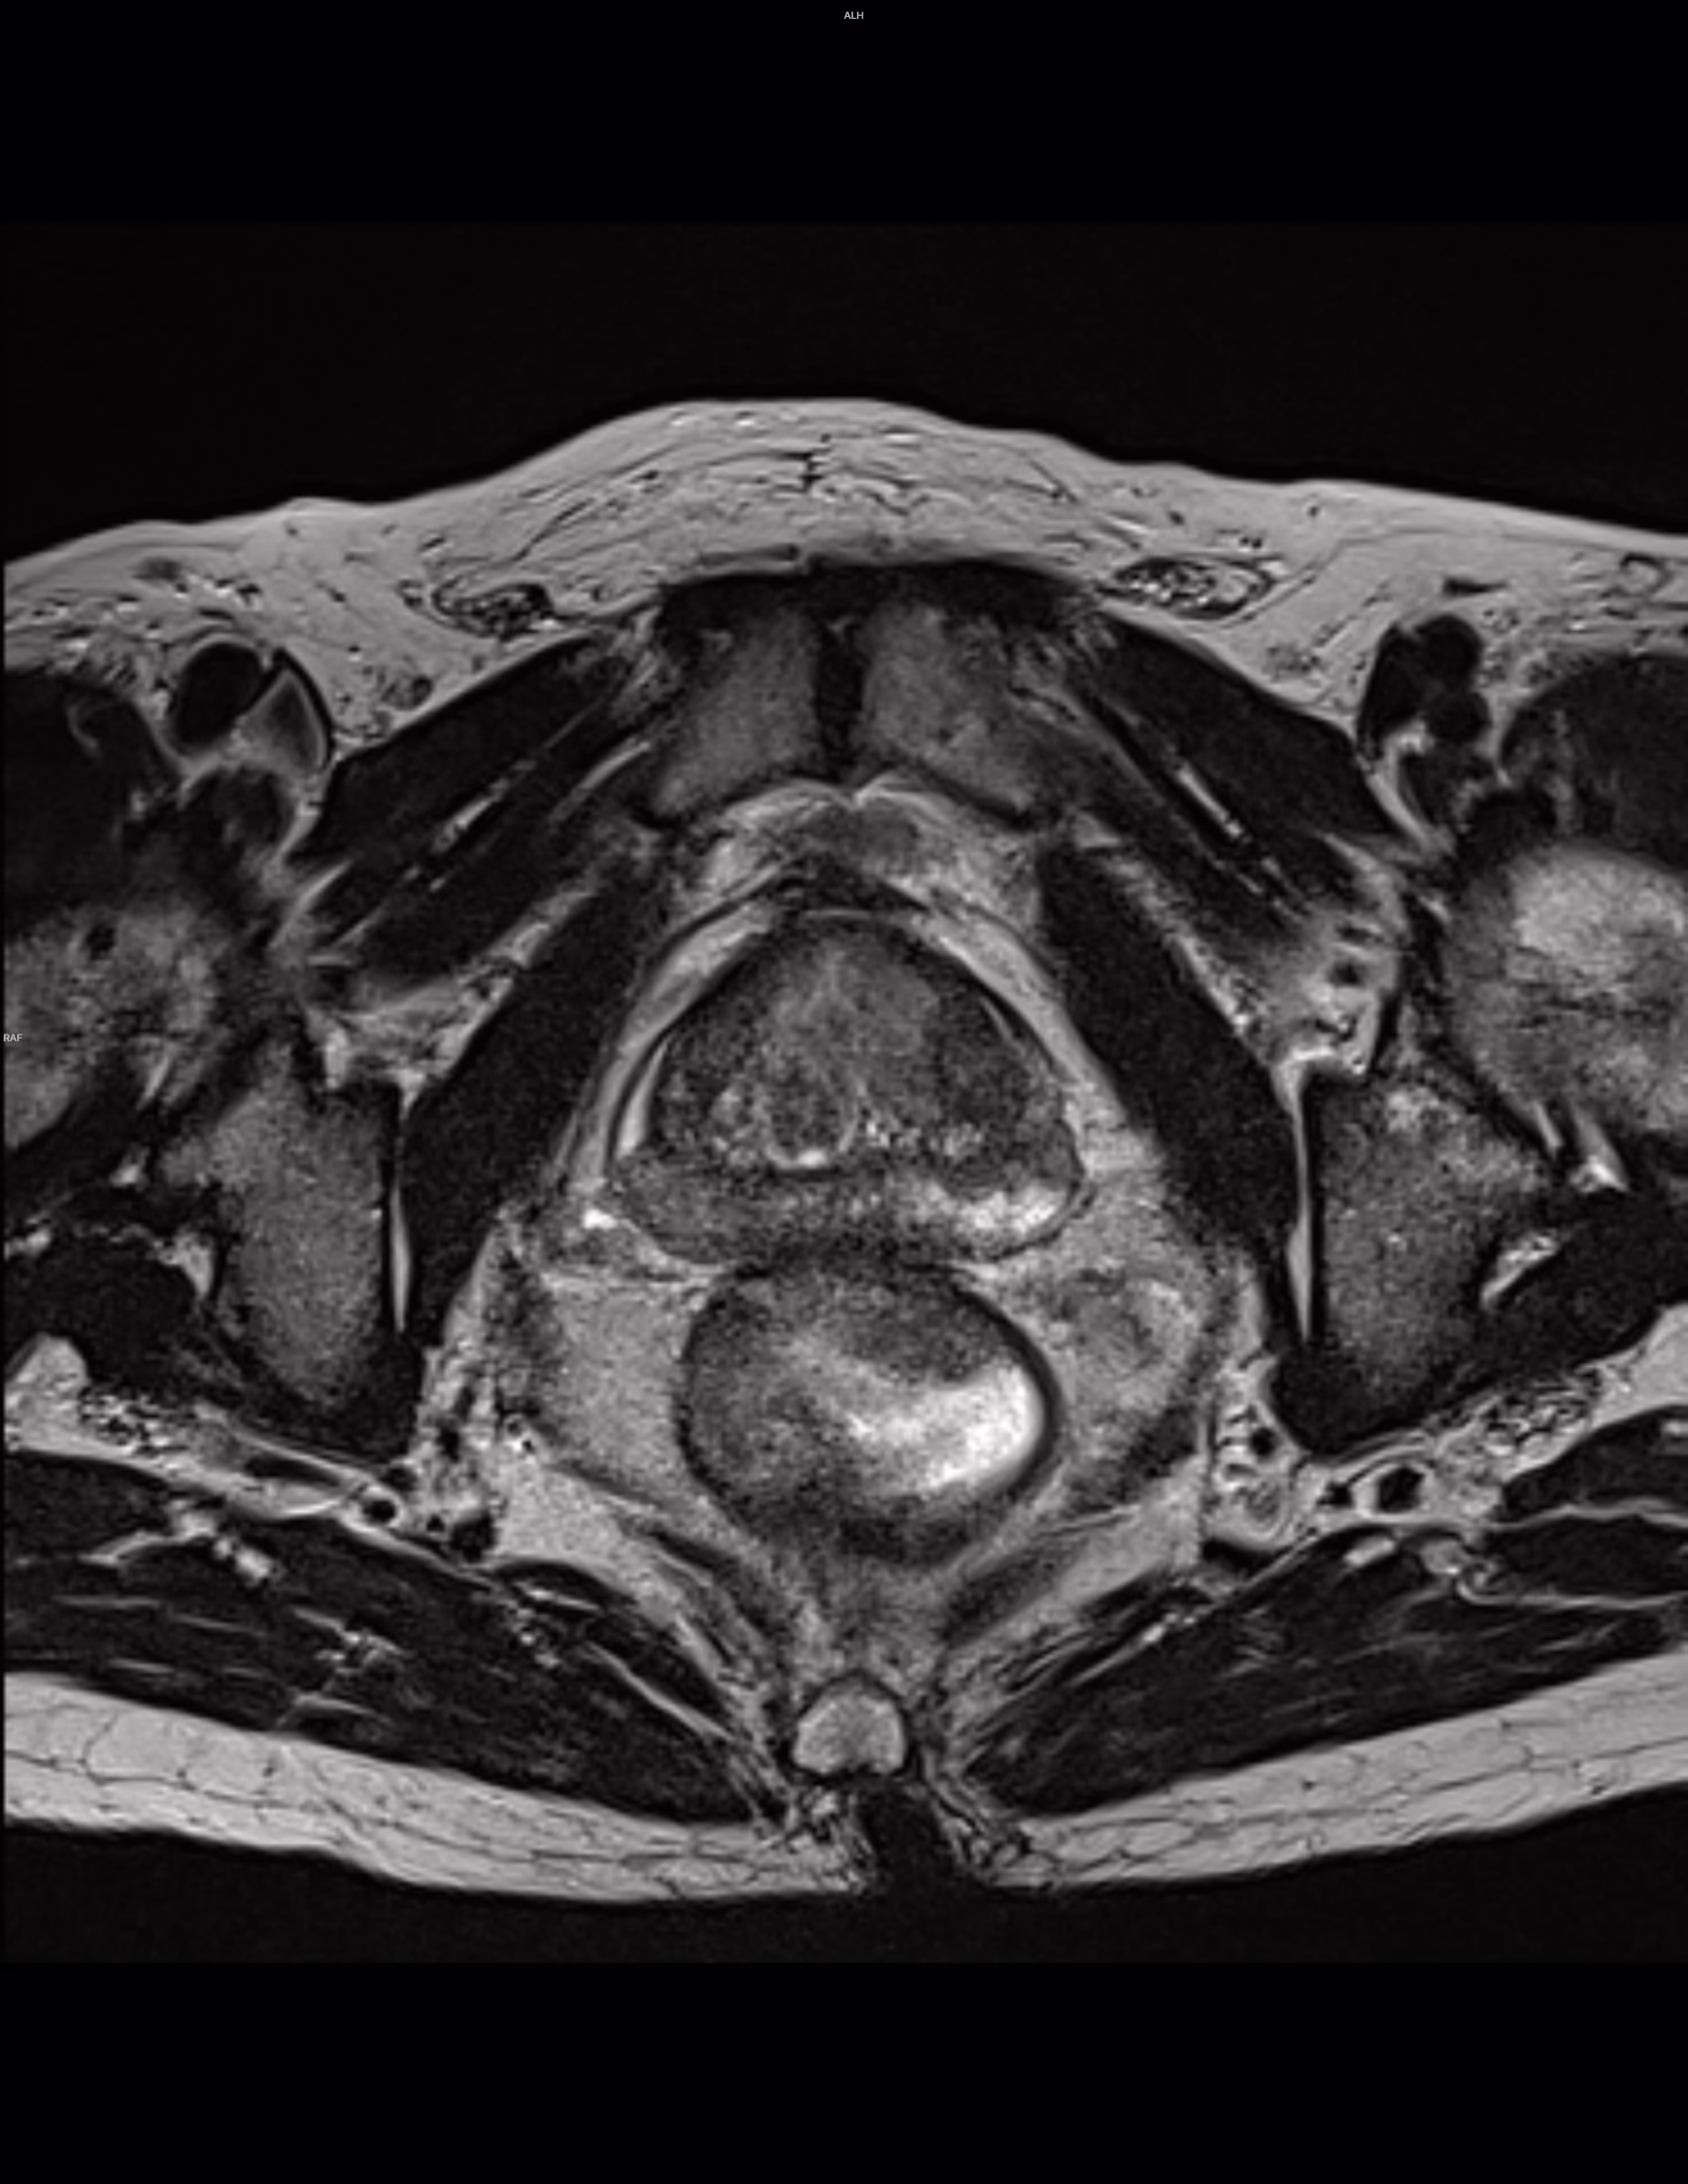

Tamaño de la próstata: 56 mm transverso x 36 mm AP x 4.7 mm de longitud con volumen total de: 50 cm³. Longitud de la uretra membranosa de 10 mm. Ápice tipo A.

Se observan cambios por hipertrofia prostática con patrón de crecimiento tipo III (transicional bilateral y retroureteral), con protrusión del lóbulo medio hacia el piso vesical en 12 mm (IPP grado 3).

Zona de Transición:

En ambas zonas transicionales destacando del lado izquierdo a nivel anterior y medial corresponde a un nódulo hiperplásico de contornos definidos que muestra cambios hemáticos como hiperintensidad en T1 y T1-FATSAT.

T2: Se observan nódulos hiperplásicos encapsulados y parcialmente encapsulados. Categoría 2/5.

DWI: Hipointensidades lineales en ADC. Categoría 2/5.

DCE: Realce focal temprano negativo.

PI-RADS 2.

Hallazgos compatibles con Hiperplasia Prostática con IPP grado 3 y volumen total de 50 cm³.